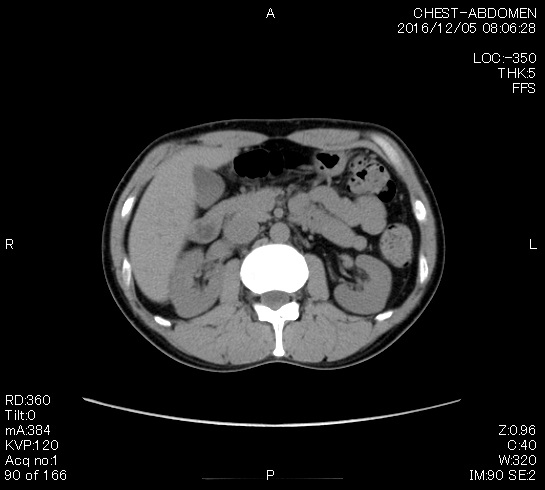

2006年入院治療の退院日から10年。 かなり大きな節目なんだが、なんだろうこの軽い感じは(笑)。 「10年生きたんだぁ」くらい。 変わったような変わっていないような。 当時は10年後なんて全く考えていなかった。 今も10年後は考えていないが・・・。 退院前日の2006/10/31は46.6kgだった。 今日計ったら54.8kg。体脂肪は16.6%。 とても健康にストレスなく生活できていることに、治療当時から現在に至るまで、関わった人全員に感謝の気持ちです。 マーカー、CT画像、問題なし!! 血液検査結果もほとんど文句なしの正常値。 そうだなぁ、数値に出ない異変としては、肩凝りかなぁ。 一旦夏になくなったと思ったが、初秋から再発。 マウスを左手にしたり、シップ貼ったり、最近はホッカイロ貼ったり。 で、一向に良くなる気配がない。 やはり四十肩なのか。 でも肩の可動域は問題ない。動かせないような痛みも無い。 結局色々考えてたどり着いたのは「変形性頚椎症」ではないかと。 肩凝りや頭痛がダラダラと続くようになるという症状がピッタリ当てはまる。 さて、改善策がなかなか難しい。 整形外科行ってもレントゲン撮って湿布をくれるだけだろう。 そんなことに大金を出すならまずは300円/回のプールで泳ごうと思う。 重力から開放して全身運動をするのが一番良いらしい。 2015年の目標は少しでも良いから水泳を再開する、だな。 マーカー、CT画像、問題なし!! 通常の血液検査結果も文句なしの正常値がズラ~っと並んだ!! 間違いなくヨメの食事のおかげである。ほんとうに感謝である!! ちなみに最近少々腰周りの肉付きが気になっていたのだが・・・。 左から2013年12月、2013年06月、2012年12月と背骨の位置は合わせて並べてみた。 6月まではあまり変化がなかったが、この半年で明らかに違う。 背中側の脂肪がやや増えてはいる。 でも最も大きな違いは、腸なのか、やたらと内臓が膨れている・・・。 一言で言うと食べすぎ?!?! 食事は野菜中心ではあるが、確かによく食べているw。 せっかくスーツのウエストを詰めたんだからこれ以上にならないようにしたい。 「腹八分目を心がける」かな。